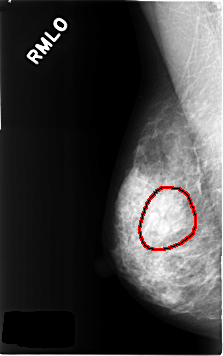

C_0314_1.RIGHT_MLO

RIGHT_MLO LINES 4616 PIXELS_PER_LINE 2896 BITS_PER_PIXEL 12 RESOLUTION 50 OVERLAY

FILE: C_0314_1.RIGHT_MLO.OVERLAY

TOTAL_ABNORMALITIES 1

ABNORMALITY 1

LESION_TYPE MASS SHAPE LOBULATED MARGINS OBSCURED

ASSESSMENT 3

SUBTLETY 4

PATHOLOGY BENIGN

TOTAL_OUTLINES 1

BOUNDARY